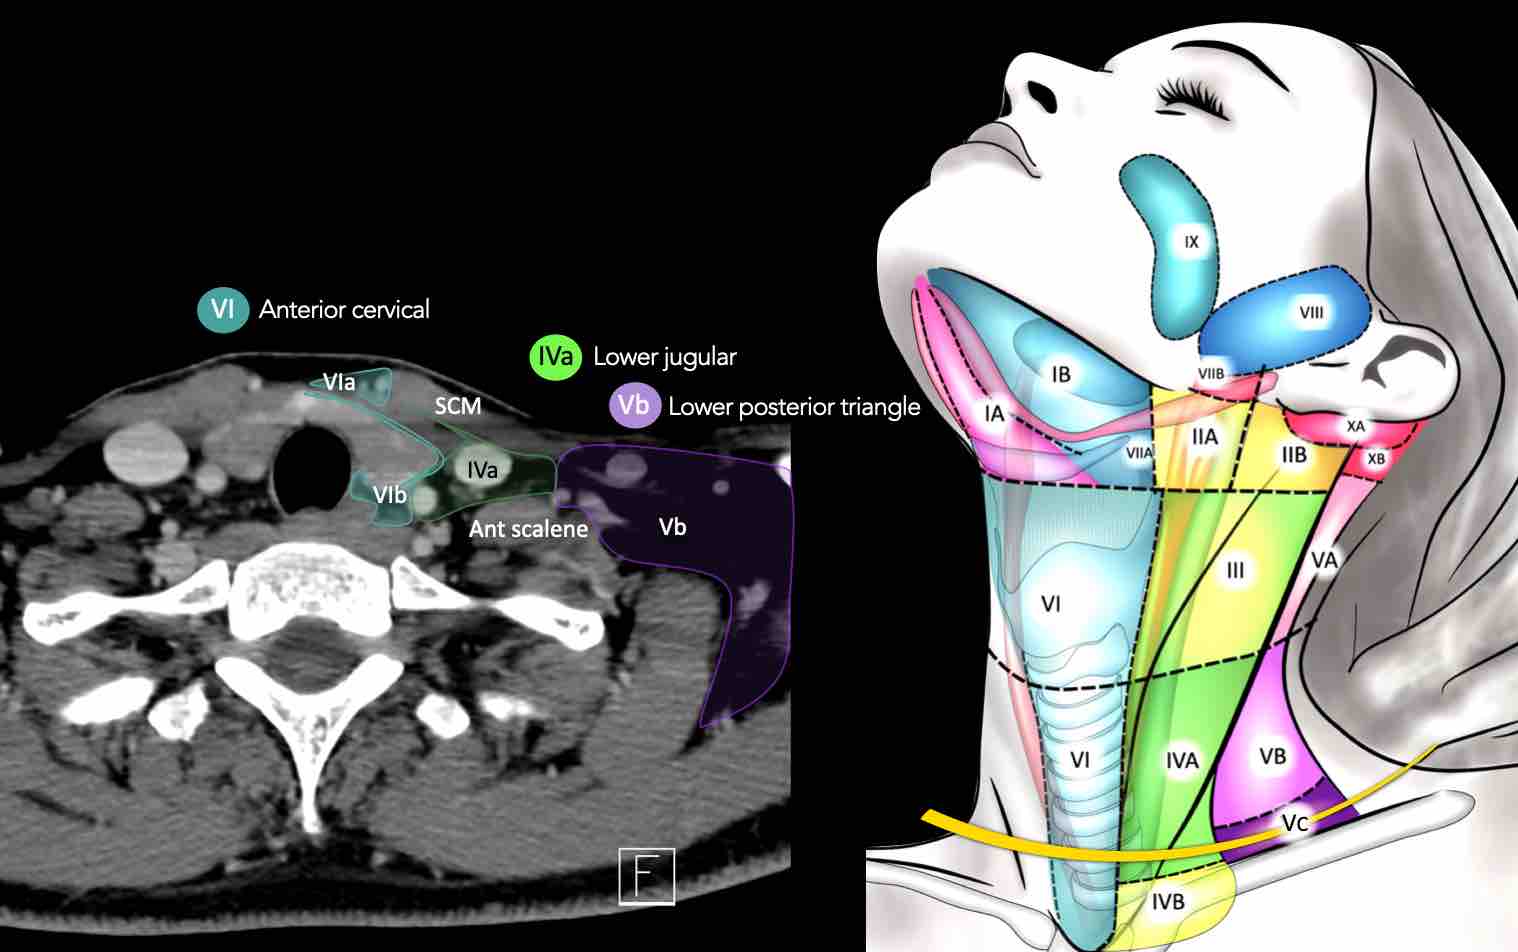

CT Scan Mặt Cắt Ngang (Axial CT)

Các lát cắt CT mặt phẳng ngang tương ứng với hình minh họa tổng quan.

Các lát cắt CT mặt phẳng ngang với hình ảnh chi tiết hơn.

Nhấp vào hình ảnh để phóng to.

IV – Tĩnh mạch cảnh dưới và hố thượng đòn trong

Ranh giới giữa tầng IVa và IVb được xác định tùy ý tại vị trí 2 cm phía trên khớp ức đòn.

Tầng IVa

Các hạch này có nguy cơ chứa di căn từ các ung thư hạ hầu, thanh quản, tuyến giáp và thực quản cổ.

Hiếm gặp hơn, di căn từ khoang miệng trước có thể biểu hiện tại vị trí này với tổn thương hạch gần tối thiểu hoặc không có.

V – Tam giác cổ sau và hố thượng đòn

Tầng V chứa các hạch của nhóm tam giác cổ sau nằm ở phía sau cơ ức đòn chũm, xung quanh phần dưới của thần kinh phụ gai sống và các mạch máu cổ ngang.

Các hạch bạch huyết ở tầng V thường liên quan nhất đến các ung thư nguyên phát của vòm hầu, hầu miệng, các cấu trúc da vùng da đầu phía sau và tuyến giáp.